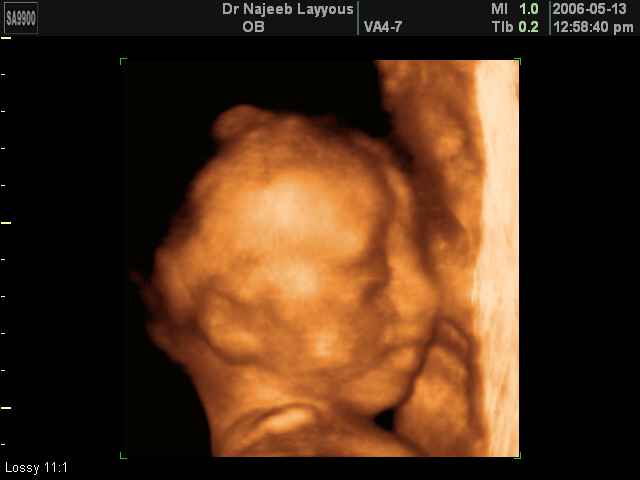

- 3D Fetal Profile Ultrasound Scan Photos

3D Fetal Profile Ultrasound Scan Photos | Dr N Layyous